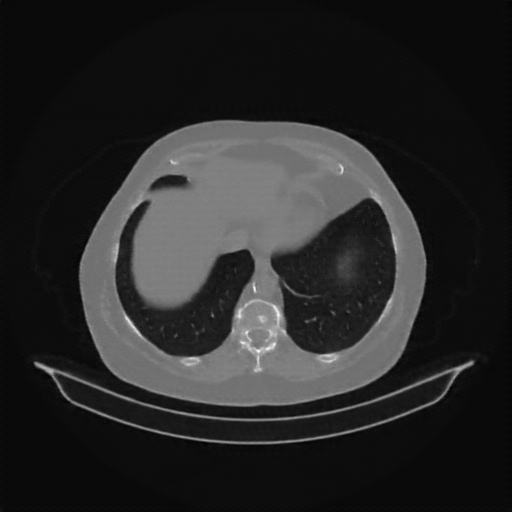

Original NATIVE CT scan (input)

No window - Raw intensity values

Lung window (WL -600, WW 1500 β†’ Low βˆ’1350, High +150)

Mediastinum window (WL 40, WW 400 β†’ Low βˆ’160, High +240)